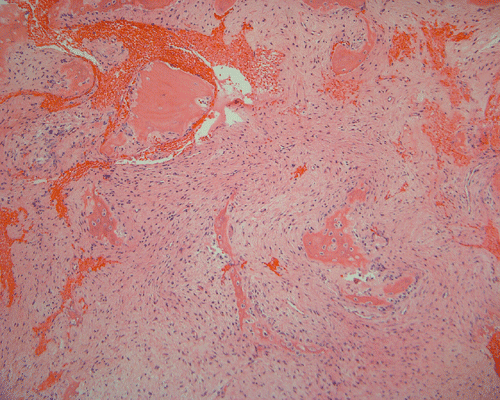

Pathology of the case: The specimen consists of multiple small pieces of irregular tissue fragments obtained by curretage. Histologically, the lesion tumor consists of bland spindled cells embedded in a collagenous matrix and arranged in a storiform pattern with frequent hemorrhage (Panel B). Entrapped residual bone associated with foci of osteoclastic type giant cells are present (Panel C). A scant number of epithelial islands are also scattered within this spindle cell background (Panel D, E, and F). On high magnification, no significant nuclear atypia or pleomorphism is noted in either the spindle cell or epithelial cell components. In other parts of the specimen, the spindle cell tumor is admixed with spiculated fragments of woven bone rimmed by osteoblasts (Panel H, I, and J). Small islandsIt of epithelial cells are also noted in these areas (Arrow in Panel H).